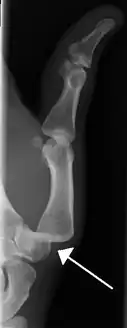

Dislocation of the left index finger

Radiograph of left index finger dislocation